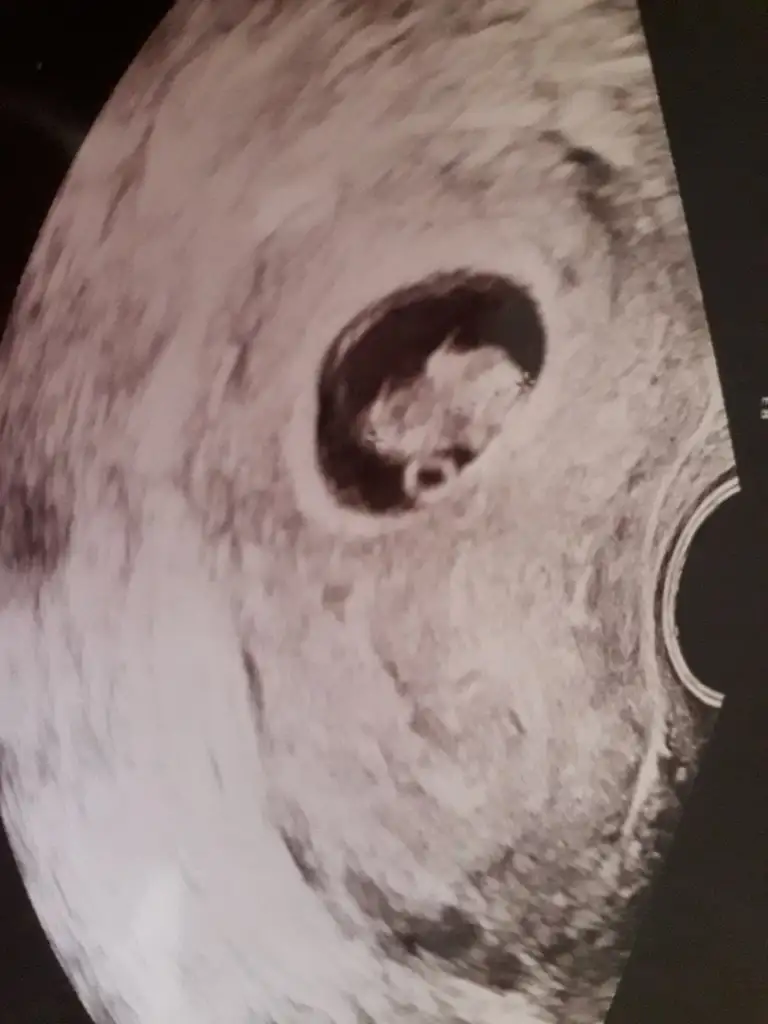

Nub icin Çok minik kese icin büyük nub icin 11 12 13 haftalar olmalı kese için 6-7 olmaliBugün yani 8+4 karından usg, kese uzun erkek mi oluyordu ben pek anlamıyorum baya uzun kese bir oğlan daha mı geliyor acaba

Buna göre erkek gibi ama en iyi 11 12 13 haftalar olmalıKarından bakıldı 7+1

6+2 karından usg

Çok net gelmedi ama bi yakınım rica etti.